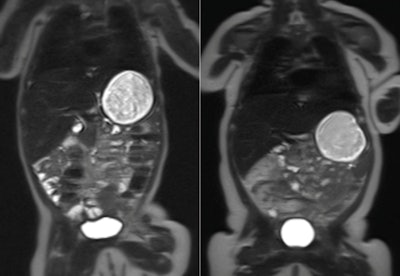

Researchers from Imperial College London used MR to measure body fat in 86 babies, acquiring images shortly after the babies were born and again when they were 8 to 12 weeks old. Forty-two of the babies had mothers with gestational diabetes, and 44 had mothers without the condition.

The babies were fed before the MRI scans, and after they fell asleep, they were given earmuffs and placed on a special beanbag before going into the scanner. Most slept through the 20-minute exam, according to the researchers.

Although babies born to mothers with gestational diabetes had no difference in body fat at birth when compared with those born to healthy mothers, at 2 months old, they had 16% more body fat than the control group.